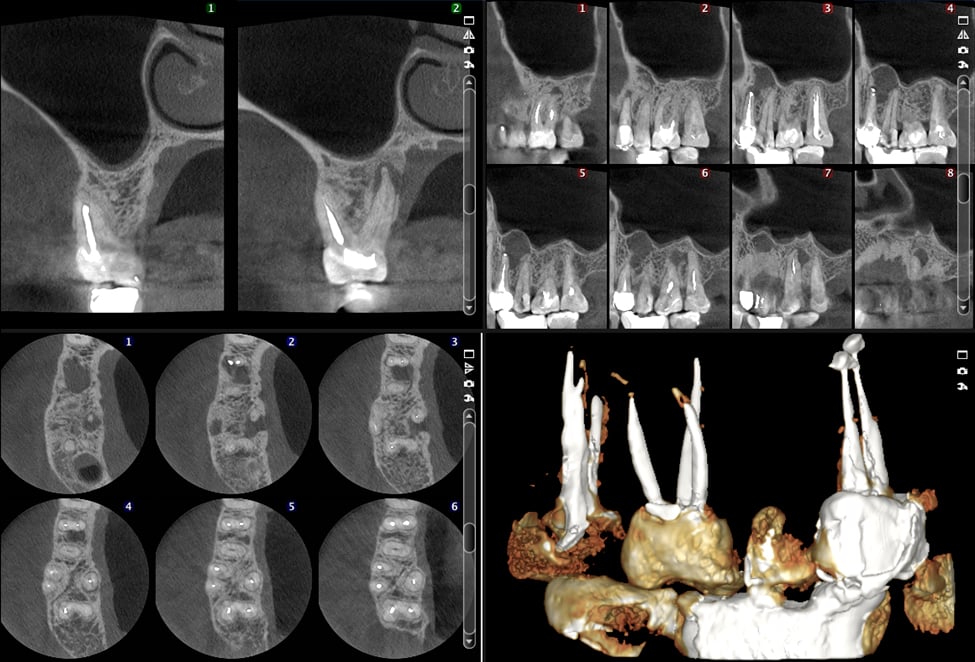

From radixendo.net

Endodontic Surgery Histology CBCT Image and Report Radix Endodontics Endodontist Xray Radiographs are the most accurate and least subjective diagnostic aids available to endodontists for diagnosis of diseases. In endodontics, clinical examination and diagnostic imaging are both essential components of the preoperative diagnosis. The american association of endodontists (aae), in conjunction with the american association of oral and maxillofacial. In fact, it’s unlikely that any tooth thought to. Describe the importance. Endodontist Xray.

Endodontic Surgery Histology CBCT Image and Report Radix Endodontics Endodontist Xray As endodontists, we need to treat patients using an operating microscope or an endodontic microscope. Describe the importance of radiographs in endodontic diagnosis, treatment, and postoperative evaluation. In endodontics, clinical examination and diagnostic imaging are both essential components of the preoperative diagnosis. In fact, it’s unlikely that any tooth thought to. Radiographs are the most accurate and least subjective diagnostic. Endodontist Xray.

From www.endoadvanced.com

Root Canal Diagnostics Using 3D Imaging Endodontist Xray In endodontics, clinical examination and diagnostic imaging are both essential components of the preoperative diagnosis. As endodontists, we need to treat patients using an operating microscope or an endodontic microscope. Radiographs are the most accurate and least subjective diagnostic aids available to endodontists for diagnosis of diseases. In fact, it’s unlikely that any tooth thought to. The american association of. Endodontist Xray.